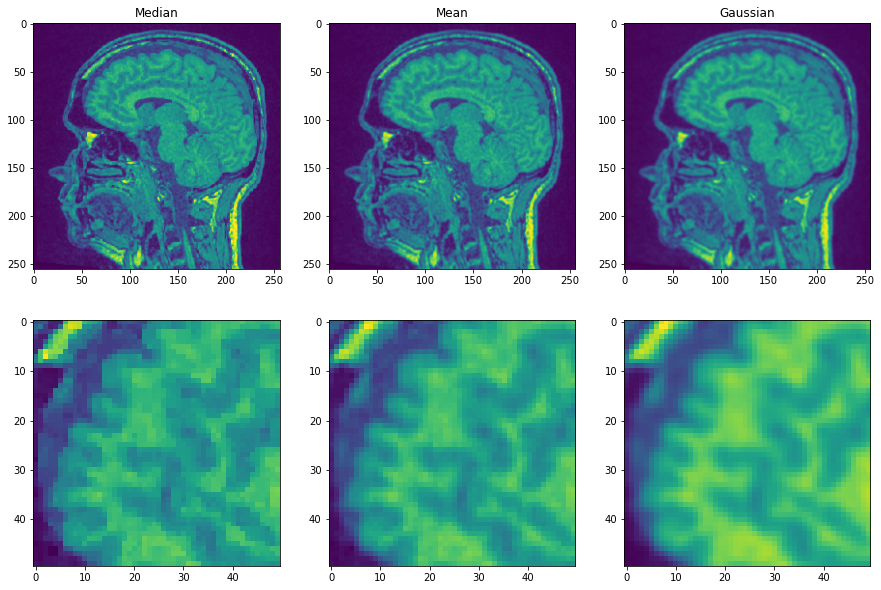

Ahora aplicamos tres filtros y comparamos las imágenes resultantes.

median_filtered = filters.median(noisy_mri, disk(1))

mean_filtered = filters.rank.mean(noisy_mri, disk(1))

gaussian_filtered = filters.gaussian(noisy_mri, sigma=1)

axs[0, 0].imshow(median_filtered)

axs[0, 0].set_title("Mediana")

axs[0, 1].imshow(mean_filtered)

axs[0, 1].set_title("Media")

axs[0, 2].imshow(gaussian_filtered)

axs[0, 2].set_title("Gaussiano")

axs[1, 0].imshow(median_filtered[50:100, 50:100])

axs[1, 1].imshow(mean_filtered[50:100, 50:100])

axs[1, 2].imshow(gaussian_filtered[50:100, 50:100])

Es posible que estés de acuerdo en que la primera imagen muestra los bordes de manera más prominente que las otras dos. Esto se debe a que el filtro de mediana preserva los bordes.